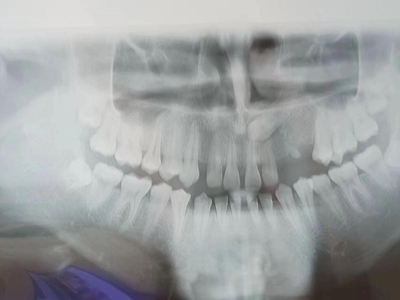

阻生牙是指由于邻牙、骨或软组织的阻碍而只能部分萌出或完全不能萌出,且以后也不能萌出的牙。引起牙阻生的成因,主要是由于颌骨缺乏足够的空间容纳全部恒牙。常见的阻生牙为下颌第三磨牙、上颌第三磨牙及上颌尖牙。

阻生牙可反复引起冠周炎,或引起邻牙牙根吸收和破坏,位置不正,不能完全萌出,好发部位是上、下颌第三磨牙。

对于阻生牙的处置需要首先明确阻生牙齿发育情况是否正常,对于由于早期外伤或其他原因造成发育异常,如牙根弯曲、短根等情况的阻生牙,还应根据患者的综合情况,决定牙齿是否保留。